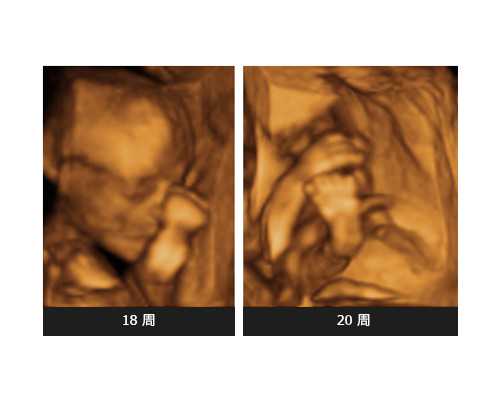

第三代试管婴儿技术,是一种针对生殖系统病患和遗传疾病风险人群的辅助生殖技术,医生将会通过人工手段在体外挑选强壮健康的卵子和精子,然后在试管中进行卵子和精子的受精过程。并且还会对于已经受精的胚胎进行一定的筛选,确定胚胎健康之后再注入到女方的体内进行培养,是一种非常可靠成熟的技术。